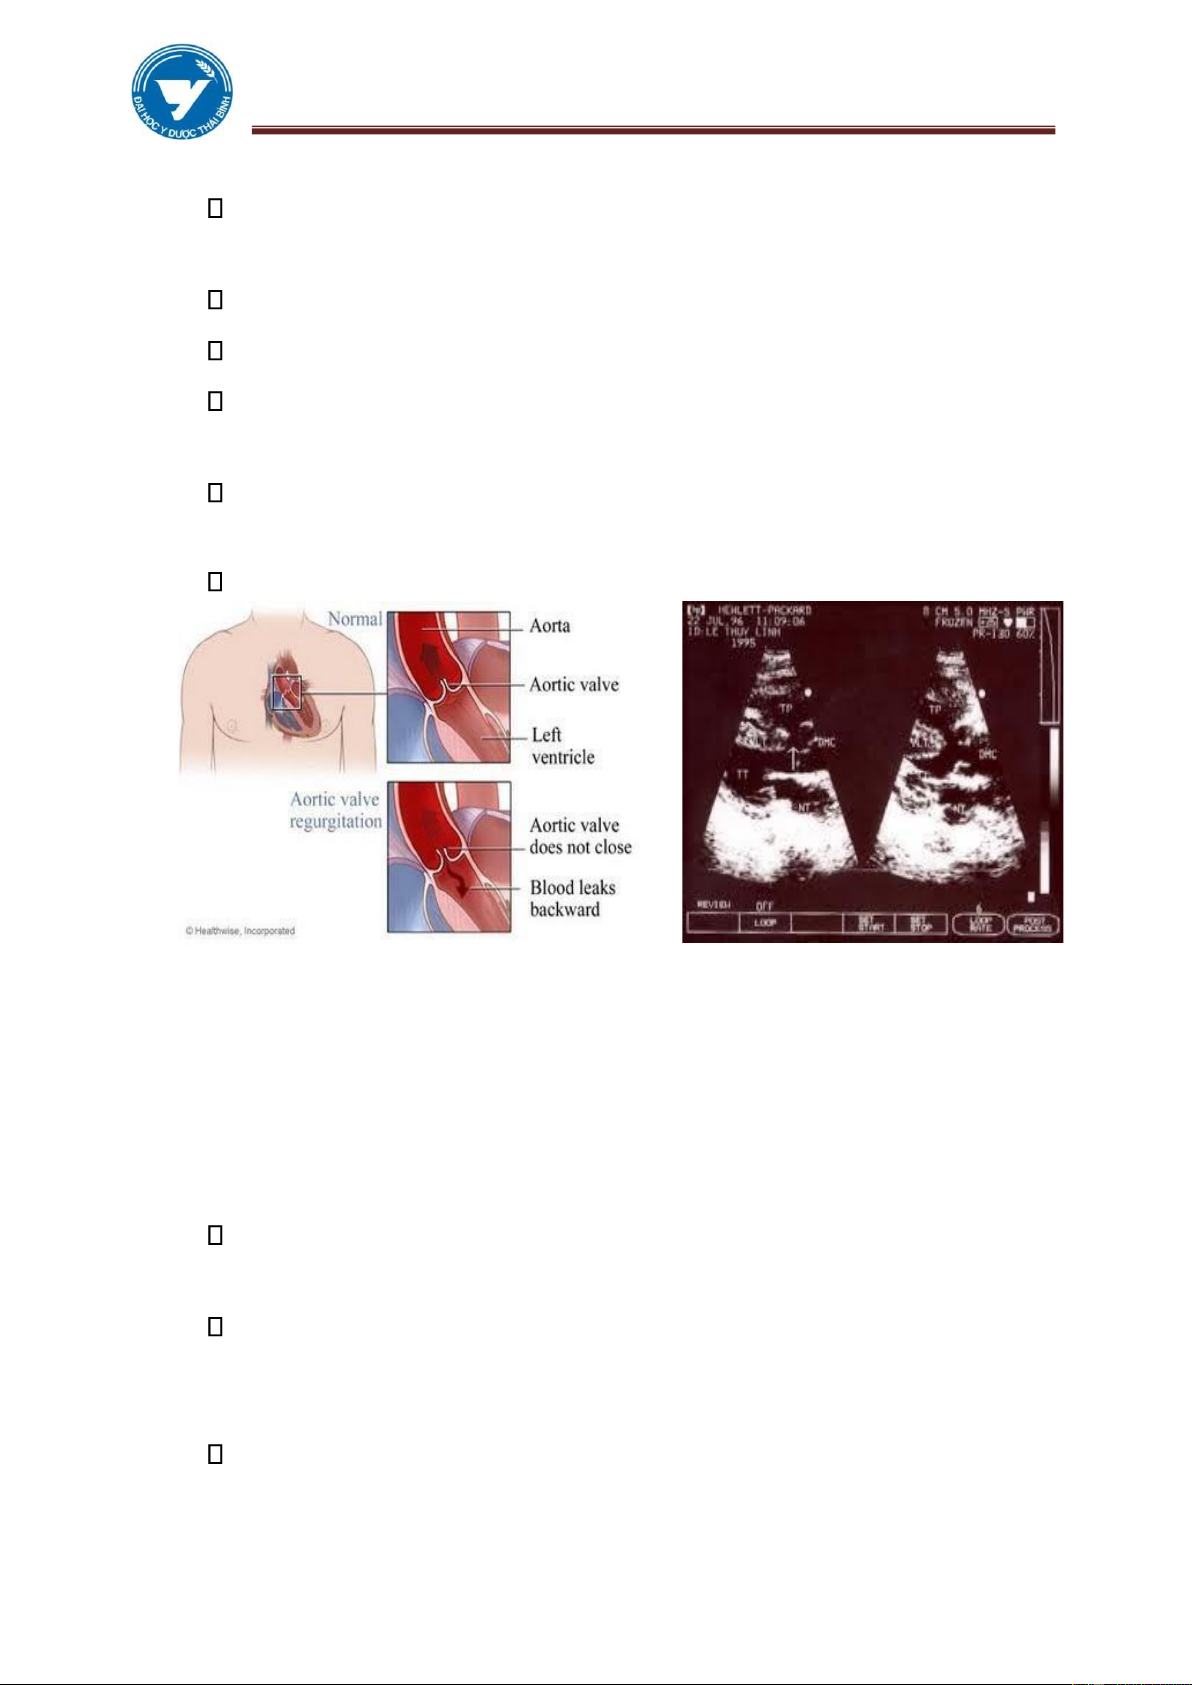

4.1. Hở van động mạch chủ

Nguyên nhân thường gặp nhất là sau thấp tim. Các nguyên nhân khác bao

gồm: Giang mai, Viêm nội tâm mạc nhiễm khuẩn, Hội chứng Marfan, Chấn

thương, ĐMC bóc tách, Viêm khớp dạng thấp.

Sinh lý bệnh: Máu phụt ngược vào thất trái trong kỳ tâm trương, tăng thể

tích, lưu lượng gây giãn buồng thất trái. Giãn vòng van 2 lá, hở van 2 lá cơ năng giãn buồng nhĩ trái. lOMoAR cPSD| 61301459

Thất trái giãn hình tròn mõm tim dưới cơ hoành trên phim thẳng, trên phim

nghiêng trái và chếch trước phải thấy chèn ép một phần ba dưới thực quản. Chỉ số T/N > 0,6.

ĐMP không to, có khi như lõm vào.

ĐMC lên thường không giãn, nếu ĐMC lên giãn rõ,phải coi chừng có kết

hợp với Hẹp van ĐMC. Quai ĐMC hầu như không thay đổi.

Siêu âm: Dấu hiệu gián tiếp đáng tin hơn là trực tiếp. Rung tâm trương của

van hai lá giãn thất trái mà không dày thành , tăng động thất trái.

Hình 3.17. Hở van ĐMC